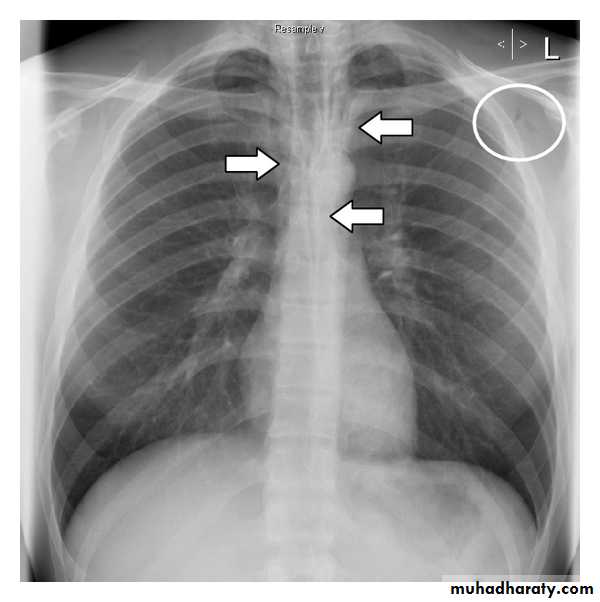

Chronic obstructive pulmonary disease (COPD):

represents a spectrum of obstructive airway diseases. It includes two key components which are chronic bronchitis-small airways disease and emphysemaChronic bronchitis (CB):

Chronic bronchitis (CB) is often defined as the presence of productive cough for 3 months in two successive years in a patient in whom other causes of chronic cough, such as tuberculosis, lung cancer and heart failure, have been excluded . It can be an important pathological compotent of chronic obstructive pulmonary disease . (often considered as a distinct phenotype of COPD)findings of chronic bronchitis on chest radiography

are nonspecific and include 1.increased HYPERLINK "http://radiopaedia.org/articles/missing?article%5btitle%5d=bronchovascular-markings" bronchovascular markings and2. HYPERLINK "http://radiopaedia.org/articles/cardiomegaly" cardiomegaly other added radiological signs

* direct signs

3.thickened peripheral airways - may only be seen in the proximal portion

*indirect signs - many of these features may be non specific on their own

1.air trapping

2.subsegmental atelectasis

3.Dirty lung appearance

Pulmonary emphysema

Pulmonary emphysema is defined as the "abnormal permanent enlargement of the airspaces distal to the terminal bronchioles accompanied by destruction of the alveolar wall and without obvious fibrosis". Emphysema is one of the entities grouped together as chronic obstructive pulmonary diseaseRadiographic features

Plain filmExcept in the case of very advanced disease with bulla formation, chest radiography does not image emphysema directly, but rather infers the diagnosis due to associated features :

hyperinflation:

1.flattened hemidiaphragm(s): most reliable sign

2.ncreased and usually irregular radiolucency of the lungs

3.increased retrosternal airspace

4.increased antero-posterior diameter of chest

5.widely spaced ribs

6.sternal bowing

7.tenting of the diaphragm

8.saber-sheath trachea

9.vascular changes paucity of blood vessels ( absent pulmonary markings in outer 1/3 of the lung fields )

10 .pulmonary arterial hypertension

pruning of peripheral vessels

increased calibre of central arteries

right ventricular enlargement